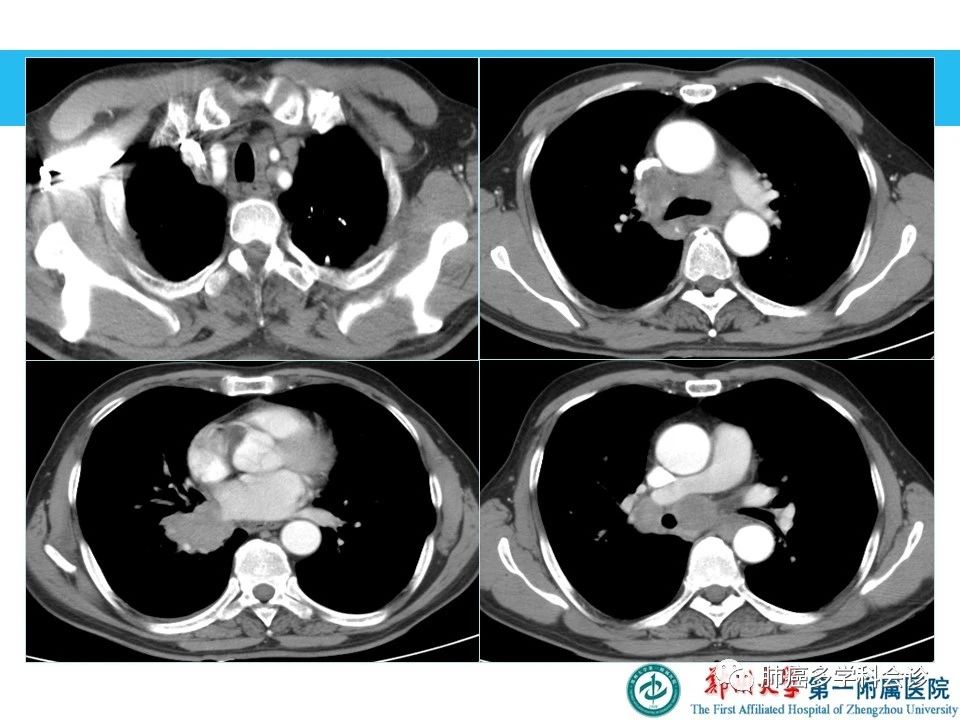

总结,肺部肿块与结节定性诊断:

典型病变:依据典型影像特征,可以做出明确诊断

非典型病变(良恶性征象交叉):手术或穿刺活检,病理定性

影像、病理、临床相结合,提高定性诊断准确率

来源:肺癌多学科会诊